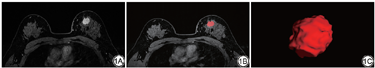

将自PACS(picture archiving and communication systems, PACS)系统导出的DICOM(digital imaging and communication in medicine, DICOM)格式的乳腺DCE-T1WI序列中的第3期图像导入ITK-SNAP软件(Version 3.8.0,http://www.itk-snap.org),并逐层对肿瘤感兴趣区(region of interest, ROI)进行手工勾画(图1)。病灶区的ROI先由一名从事乳腺影像诊断5年以上的放射科医师在不知病理结果的情况下进行勾画,再由至少10年工作经验的副主任医师进行ROI校对,如存在差异则由更高资历的乳腺放射科医生确定最终的ROI。